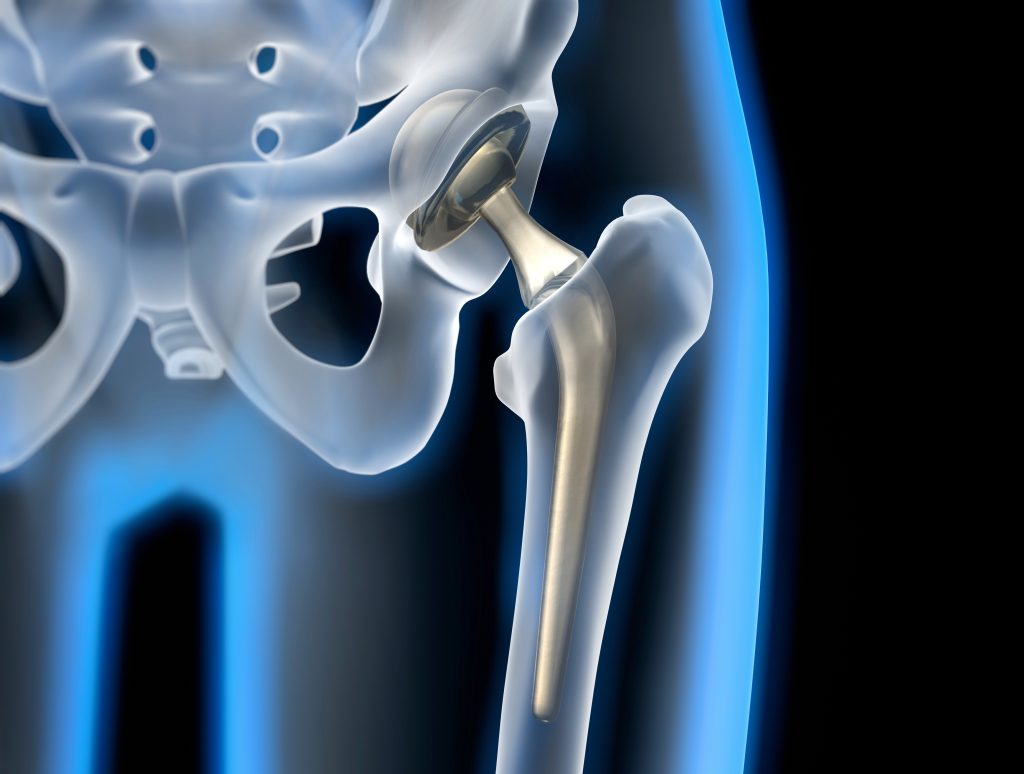

Hüfttotalendprothese

Bei fortgeschrittener Coxarthrose, die zu starken Schmerzen und Bewegungseinschränkungen führt, kann eine Hüfttotalendprothese (Hüft-TEP) eine wirksame Behandlungsoption sein. Hierbei werden sowohl der Hüftkopf als auch die Gelenkspfanne komplett durch eine Prothese ersetzt, um die Schmerzen zu lindern und die Beweglichkeit wiederherzustellen. Durch einen minimalinvasiven, gewebeschonenden Eingriff können Patienten sehr rasch wieder mobilisiert werden. Das Gelenk ist nach erfolgreicher Operation wieder voll belastbar und sporttauglich.

Die Operation wird in der Regel unter Vollnarkose oder regionaler Betäubung durchgeführt, um Schmerzen während des Eingriffs zu verhindern. Der Chirurg macht zunächst einen Schnitt in der Nähe der Hüfte, um Zugang zum Hüftgelenk zu erhalten. Sobald Zugang zum Hüftgelenk besteht, wird der beschädigte Teil des Gelenks präzise entfernt, wobei darauf geachtet wird, so viel gesundes Gewebe wie möglich zu erhalten. Anschließend wird die künstliche Hüftprothese, welche aus Metall und Keramik oder einem abriebfesten Kunststoff besteht, welcher ein flexibles Gleiten der Gelenksflächen ermöglicht, in das Gelenk eingesetzt und verankert. Nach der Operation wird der Patient auf eine Erholungsstation gebracht, wo sein Zustand überwacht wird.